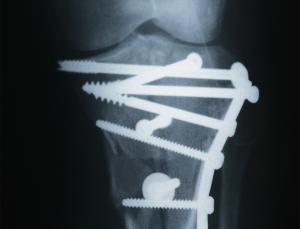

Metal alloy screws and plates can hold fractured bones together but if they start to corrode a second operation is required to remove them. Biodegradable alternatives can trigger inflammation and are time-consuming to implant – the polymers are so soft that you first have to drill a hole in the bone and fashion a helical ridge around the inside - the inner thread - to hold the screw in place.

In rats, the team found that their silk screws were tough enough to carve their own threads into bone as they are screwed into a hole, just as metal alloy screws do. The silk naturally biodegrades with time, like the polymer alternatives but without causing inflammation.